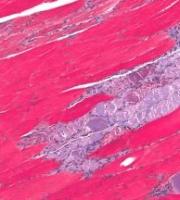

SANTÉ MUSCULAIRE: La préserver avec l'âge en bloquant la myostatine